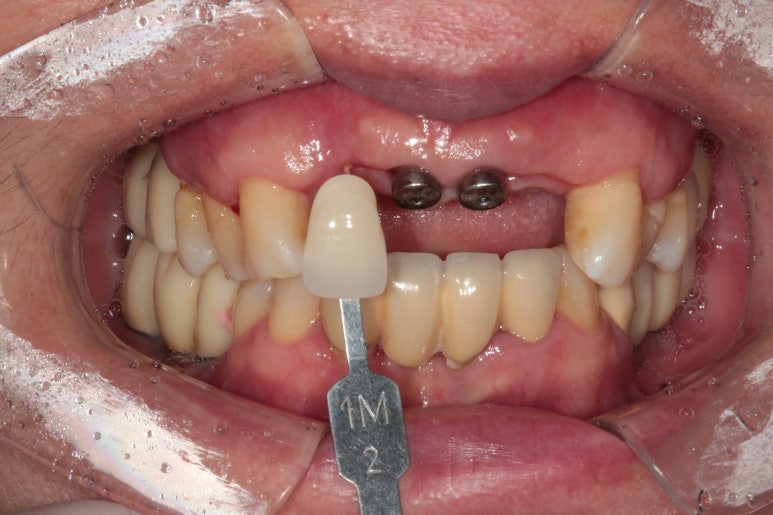

저희 신금호역 치과 백원장은 치아 색상표를 사용하여 색상동 꼼꼼하게 본답니다.!!!!

임플란트에 기둥을 연결하고 임시치아를 붙여드렸습니다.

앞니 임플란트이기 때문에 모양도 상당히 중요한데요,

보시는 것은 임시치아이며, 약간은 네모반듯한 모양이었어요.

굳이 임시치아를 만들어드리는 이유는, 색상도 살펴보고 모양도 살펴볼 시간이 필요하기 때문입니다.

색상을 조금 더 밝게 하길 원하셔서 최종 크라운은 더 밝게 제작해보기로 하였어요.